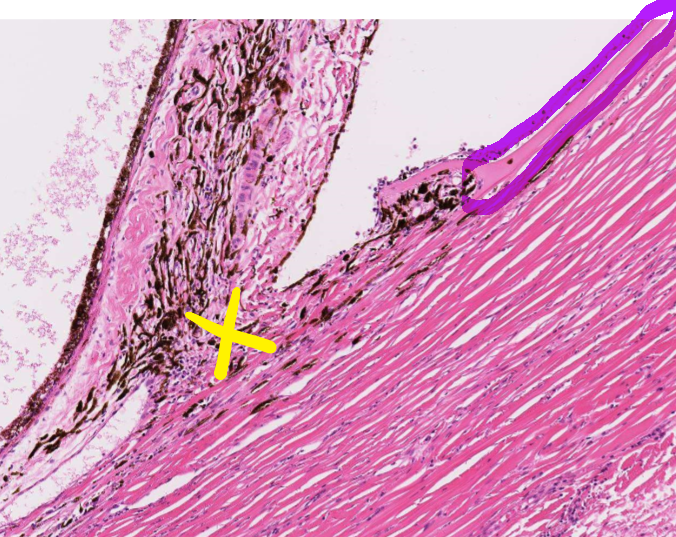

4

Q

This is normal, healthy tissue of the eye.

What are the highlighted structures?

Green = ____

Yellow = ____

Blue = ____

A

Green = trabecular meshwork

Yellow = pectinate ligament

Blue = descemet’s membrane